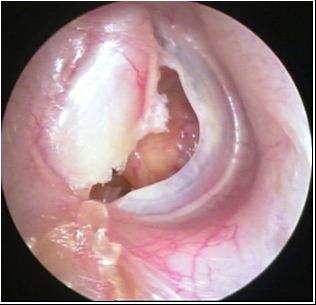

JFC Otitis media crónica colesteatomatosa

JFC Otitis media crónica colesteatomatosa.